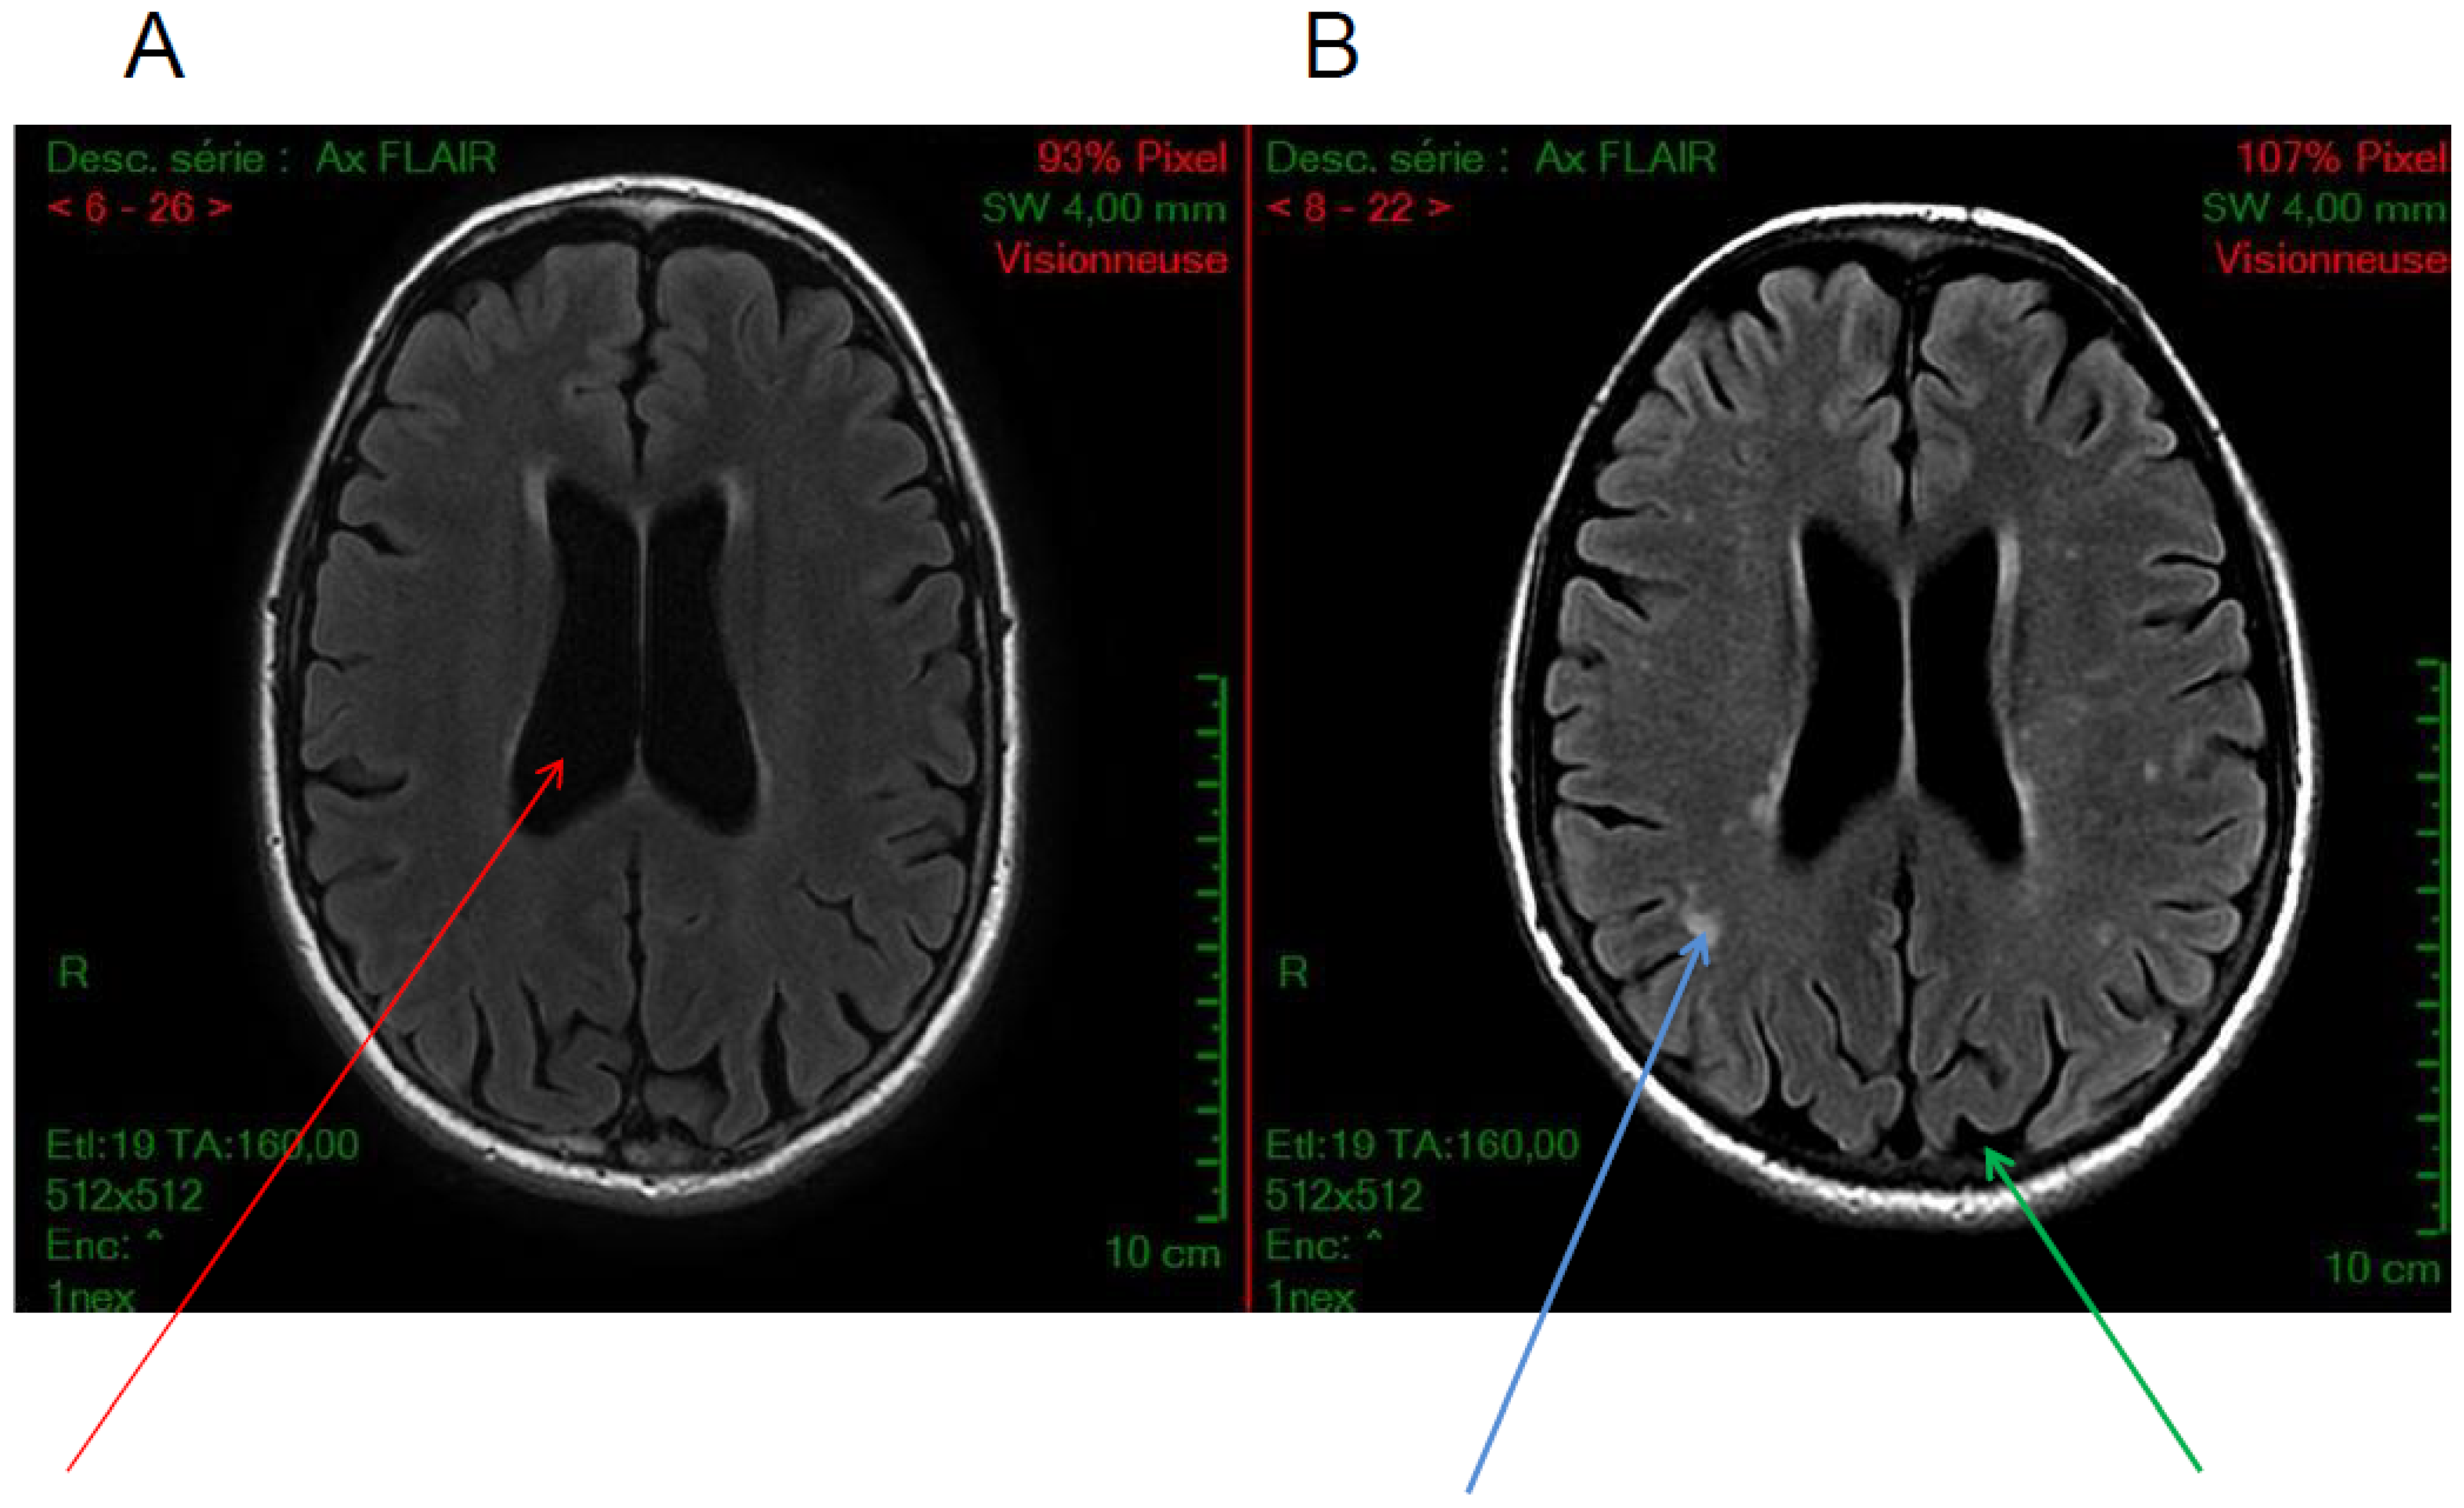

Figure 2.

Axial FLAIR sequences. Examples of brain MRI anatomical images of cystinosis patients showing (A) an isolated ventricular dilatation (red arrow), (B) in another patient, cortical atrophy (green arrow) and diffuse white matter anomalies (blue arrow) associated with ventricular dilatation, (C–F) diffuse subcortical white matter hyperintensities, and (G,H) Wirshow or perivascular space enlargement (blue arrow)(images from N. Boddaert, Necker hospital).

Cortical atrophy is the most frequent radiological finding in cystinosis patients. By computed tomography (CT) scan or magnetic resonance imaging (MRI), cortical atrophy is observed in almost all patients with CNS symptoms [7]. Cerebral atrophy is also reported in patients without important CNS clinical abnormality and in patients with minor alterations in cognitive performance, in particular with impairment of visual memory [15,36,39]. In a recent study, among patients with infantile cystinosis, 72% showed evidence of cortical atrophy, 67% central atrophy (ventriculomegaly), and 50.0% demonstrated both (Figure 2) [17]. In that study, only two patients with infantile cystinosis had a normal brain MRI, both being the youngest patients included. Interestingly, no atrophy was observed in patients with late-onset cystinosis, even if the patients analyzed were older than the other cystinosis patients. Importantly, such atrophy was specifically observed in cystinosis patients, and not in controls with nephropathy. In another study, also including younger patients, cystinosis patients presented significantly more atrophy than age- and sex-matched healthy controls in the frontal, parietal, temporal, and occipital regions, the corpus callosum, and the cerebellum [35]. It is worth noticing that atrophy was localized in parieto-occipital regions, which is consistent with the visuo-spatial-specific impairment described in these patients.

5.3. White Matter Hyperintensities

White matter hyperintensities can be observed in 50% of cystinosis patients, including in patients with adolescent onset cystinosis (Figure 2) [17,35]. However, we have recently shown that these hyperintensities can also be observed in other patients with chronic renal failure [17]. White matter anomalies have been reported in some previous studies [7,40]. Interestingly, white matter abnormalities have been described in adults with chronic kidney disease compared to controls, suggesting that chronic kidney disease may result in a brain phenotype consistent with accelerated aging [35,41,42]. These results demonstrate the importance of adding a control group with renal failure when investigating brain abnormalities in cystinosis patients.